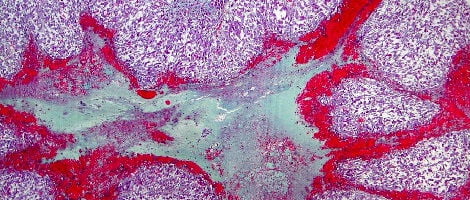

Nesta fase pós-ovulação o folículo roto transforma-se num corpo amarelo denominado “corpo lúteo”. Este corpo é o responsável pela produção de estrogénio e progesterona, hormonas que vão actuar sobre o endométrio.

A progesterona modifica a mucosa cervical no colo do útero tornando-o impenetrável para os espermatozóides. Actua, também, sobre as paredes do útero que se tornam esponjosas e grossas devido ao maior fluxo sanguíneo e que ficam, assim, preparadas para receber o óvulo fertilizado.

O corpo lúteo produz estas duas hormonas até a oitava semana de gestação e , a partir desse momento, é a placenta que as produz.